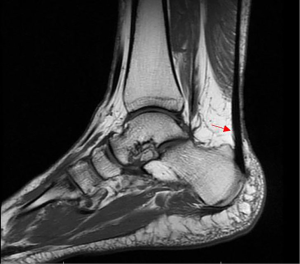

Synovitis was defined as synovial membrane thickening in T1-boosted sequences and increased signals in T2-boosted sequences (35). Representative MRI imagines are presented in Figures 1-10 in order to illustrate the definition of each condition.